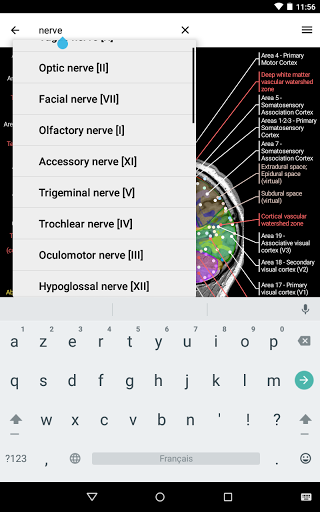

* اعثر على الأجزاء التشريحية الخاصة بك بسهولة أكبر بفضل ميزة البحث الجديدة والأكثر سهولة وقوة

* تحسين أداء البحث عن البنية التشريحية